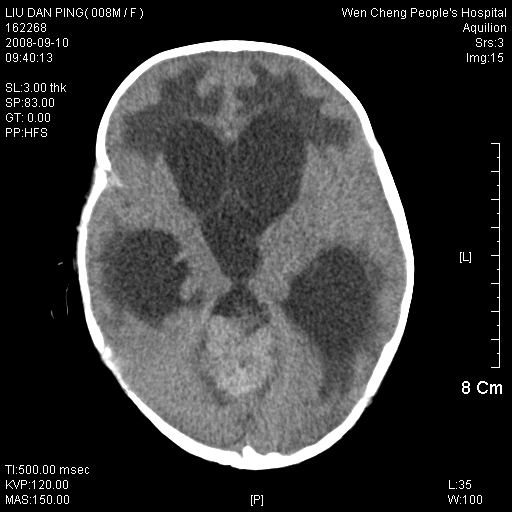

以下是引用深泽交通医院在2008-9-10 15:08:00的发言:[br]髓母瘤并脑积水

以下是引用卜一在2008-9-10 16:21:00的发言:[br]髓母细胞瘤伴梗阻性脑积水!支持![br]髓母细胞瘤特点:—般直径大于3.5cm,位于后颅凹中线之小脑蚓部。累及上蚓部的肿瘤延伸到小脑幕切迹之上,ct平扫肿瘤多呈均匀一致的高或等密度病灶,增强检查呈均匀一致的强化。病灶中有小坏死时,平扫亦可呈不均匀之混杂密度,注药后有增强。[br]

以下是引用yuhongjun在2008-9-10 16:57:00的发言:[br]髓母细胞瘤伴梗阻性脑积水.

以下是引用lirenxiong在2008-9-10 18:47:00的发言:[br]教科书般经典!谢谢!

以下是引用zjzjr在2008-9-10 15:09:00的发言:[br]髓母细胞瘤伴梗阻性脑积水.